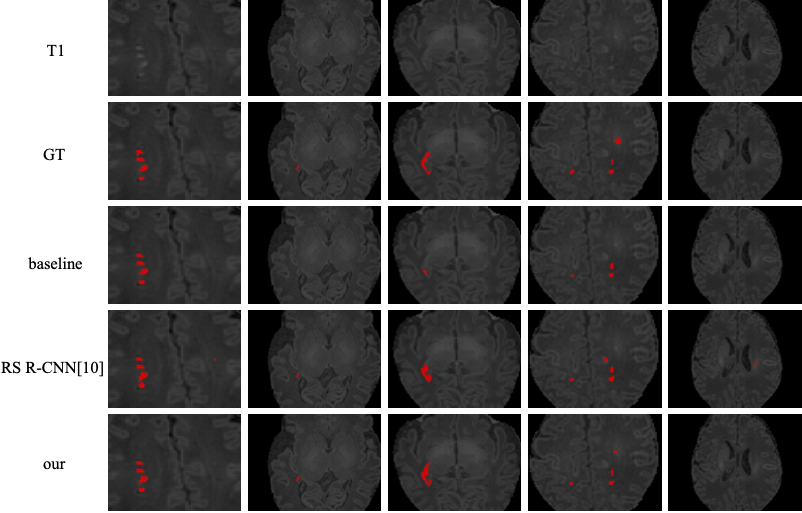

我们针对这一问题提出利用反事实推理的思想,结合脑组织分割的辅助任务来学习该病变的精细的位置信息和形态表征,以实现准确的定位和分割。其中反事实推理可以为病变分割提供初步的病变“定位”指导,而脑组织分割任务中自然包含了和病变分割任务相关的解剖先验知识和位置引导。

基于此,我们设计了一个简单且有效的深度学习框架(即DeepPWML)。它结合病变反事实图和组织分割概率图以及原始MR图像中蕴含的外观信息,实现了点状白质病变的精细分割,并在真实临床婴儿T1w MR图像的数据集上取得了最先进的效果。